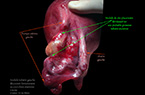

Grossesse extra-utérine tubaire ancienne et méconnue, sur laquelle évolue un nodule du site placentaire - découverte fortuite lors d'une césarienne Grossesse extra-utérine tubaire ancienne et méconnue, sur laquelle évolue un nodule du site placentaire - découverte fortuite lors d'une césarienne Grossesse extra-utérine tubaire ancienne et méconnue, sur laquelle évolue un nodule du site placentaire - découverte fortuite lors d'une césarienne